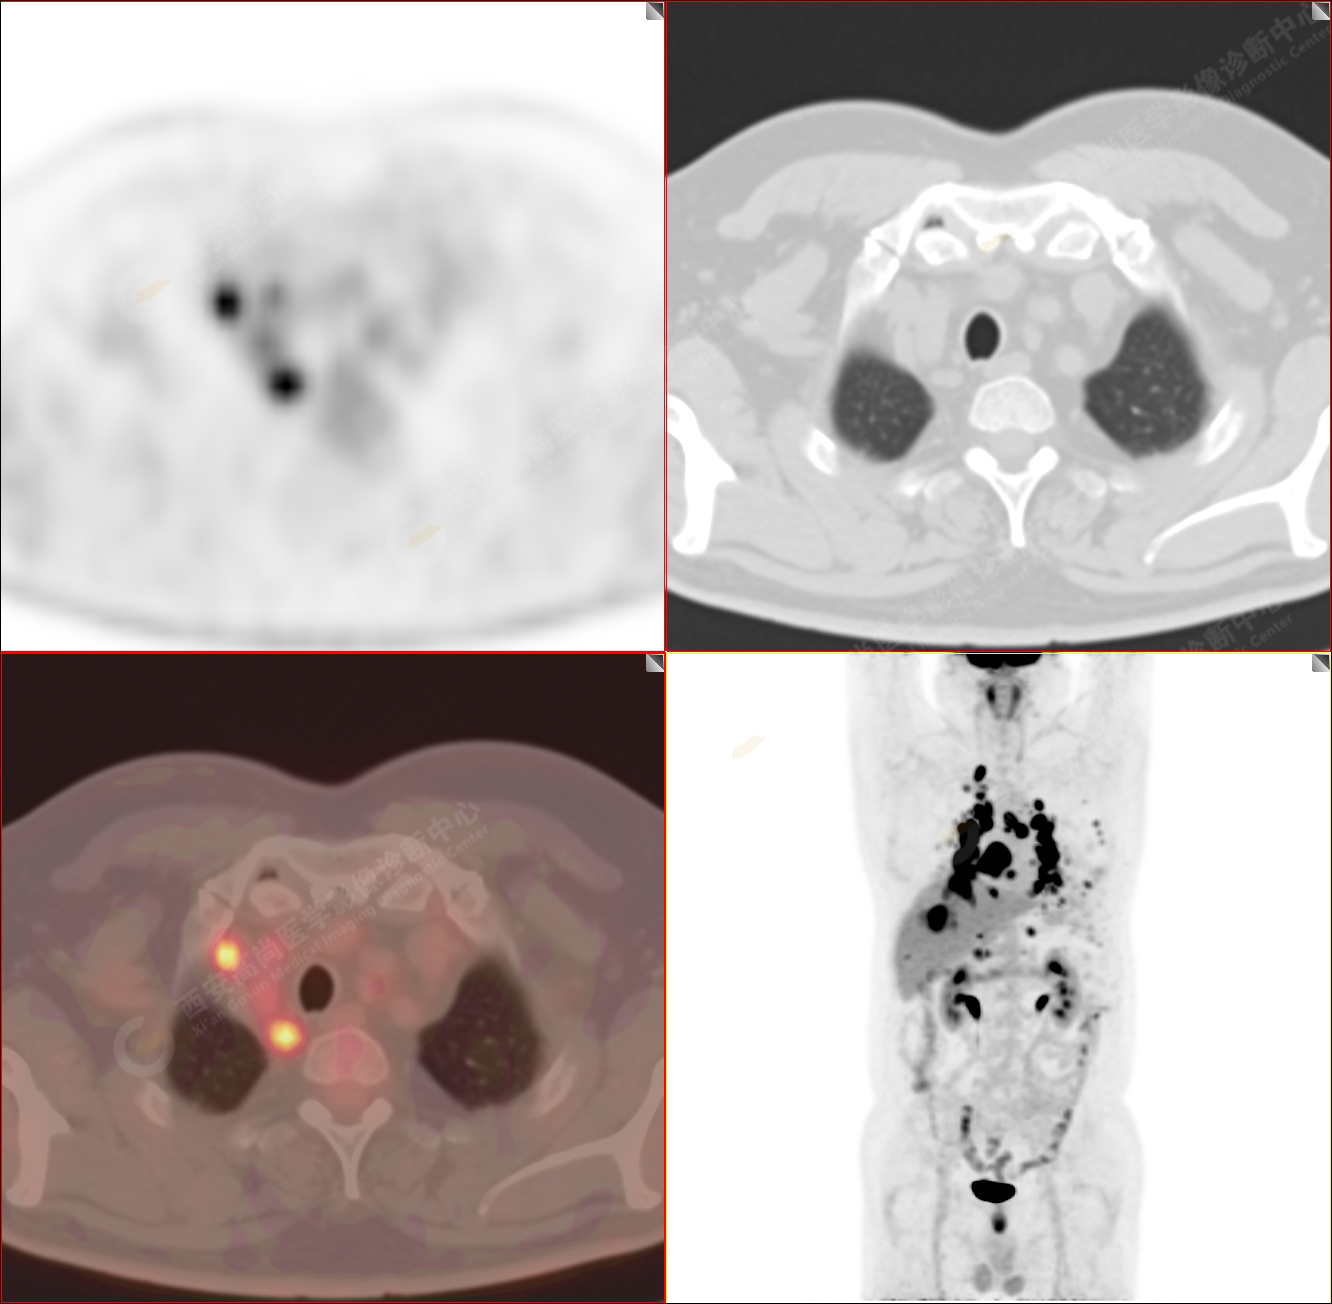

男性,53歲,頭暈半月入院,CT發(fā)現(xiàn)肺內(nèi)腫塊,雙肺多發(fā)大小不等實(shí)性及粟粒樣結(jié)節(jié),雙肺門(mén)及縱隔多發(fā)腫大淋巴結(jié)。病程中無(wú)發(fā)熱、胸悶氣及胸部不適。既往:左側(cè)肋骨外傷史。

PET/CT圖像